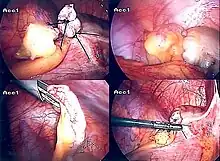

Surgery

The surgical procedure for the removal of the appendix is called an appendectomy. Appendectomy can be performed through open or laparoscopic surgery. Laparoscopic appendectomy has several advantages over open appendectomy as an intervention for acute appendicitis.[72]

Laparoscopic appendectomy

Laparoscopic appendectomy has become an increasingly prevalent intervention for acute appendicitis since its introduction in 1983.[76] This surgical procedure consists of making three to four incisions in the abdomen, each 0.25 to 0.5 inches (6.4 to 12.7 mm) long. This type of appendectomy is made by inserting a special surgical tool called a laparoscope into one of the incisions. The laparoscope is connected to a monitor outside the person's body, and it is designed to help the surgeon to inspect the infected area in the abdomen. The other two incisions are made for the specific removal of the appendix by using surgical instruments. Laparoscopic surgery requires general anesthesia, and it can last up to two hours. Laparoscopic appendectomy has several advantages over open appendectomy, including a shorter post-operative recovery, less post-operative pain, and lower superficial surgical site infection rate. However, the occurrence of an intra-abdominal abscess is almost three times more prevalent in laparoscopic appendectomy than open appendectomy.[77]